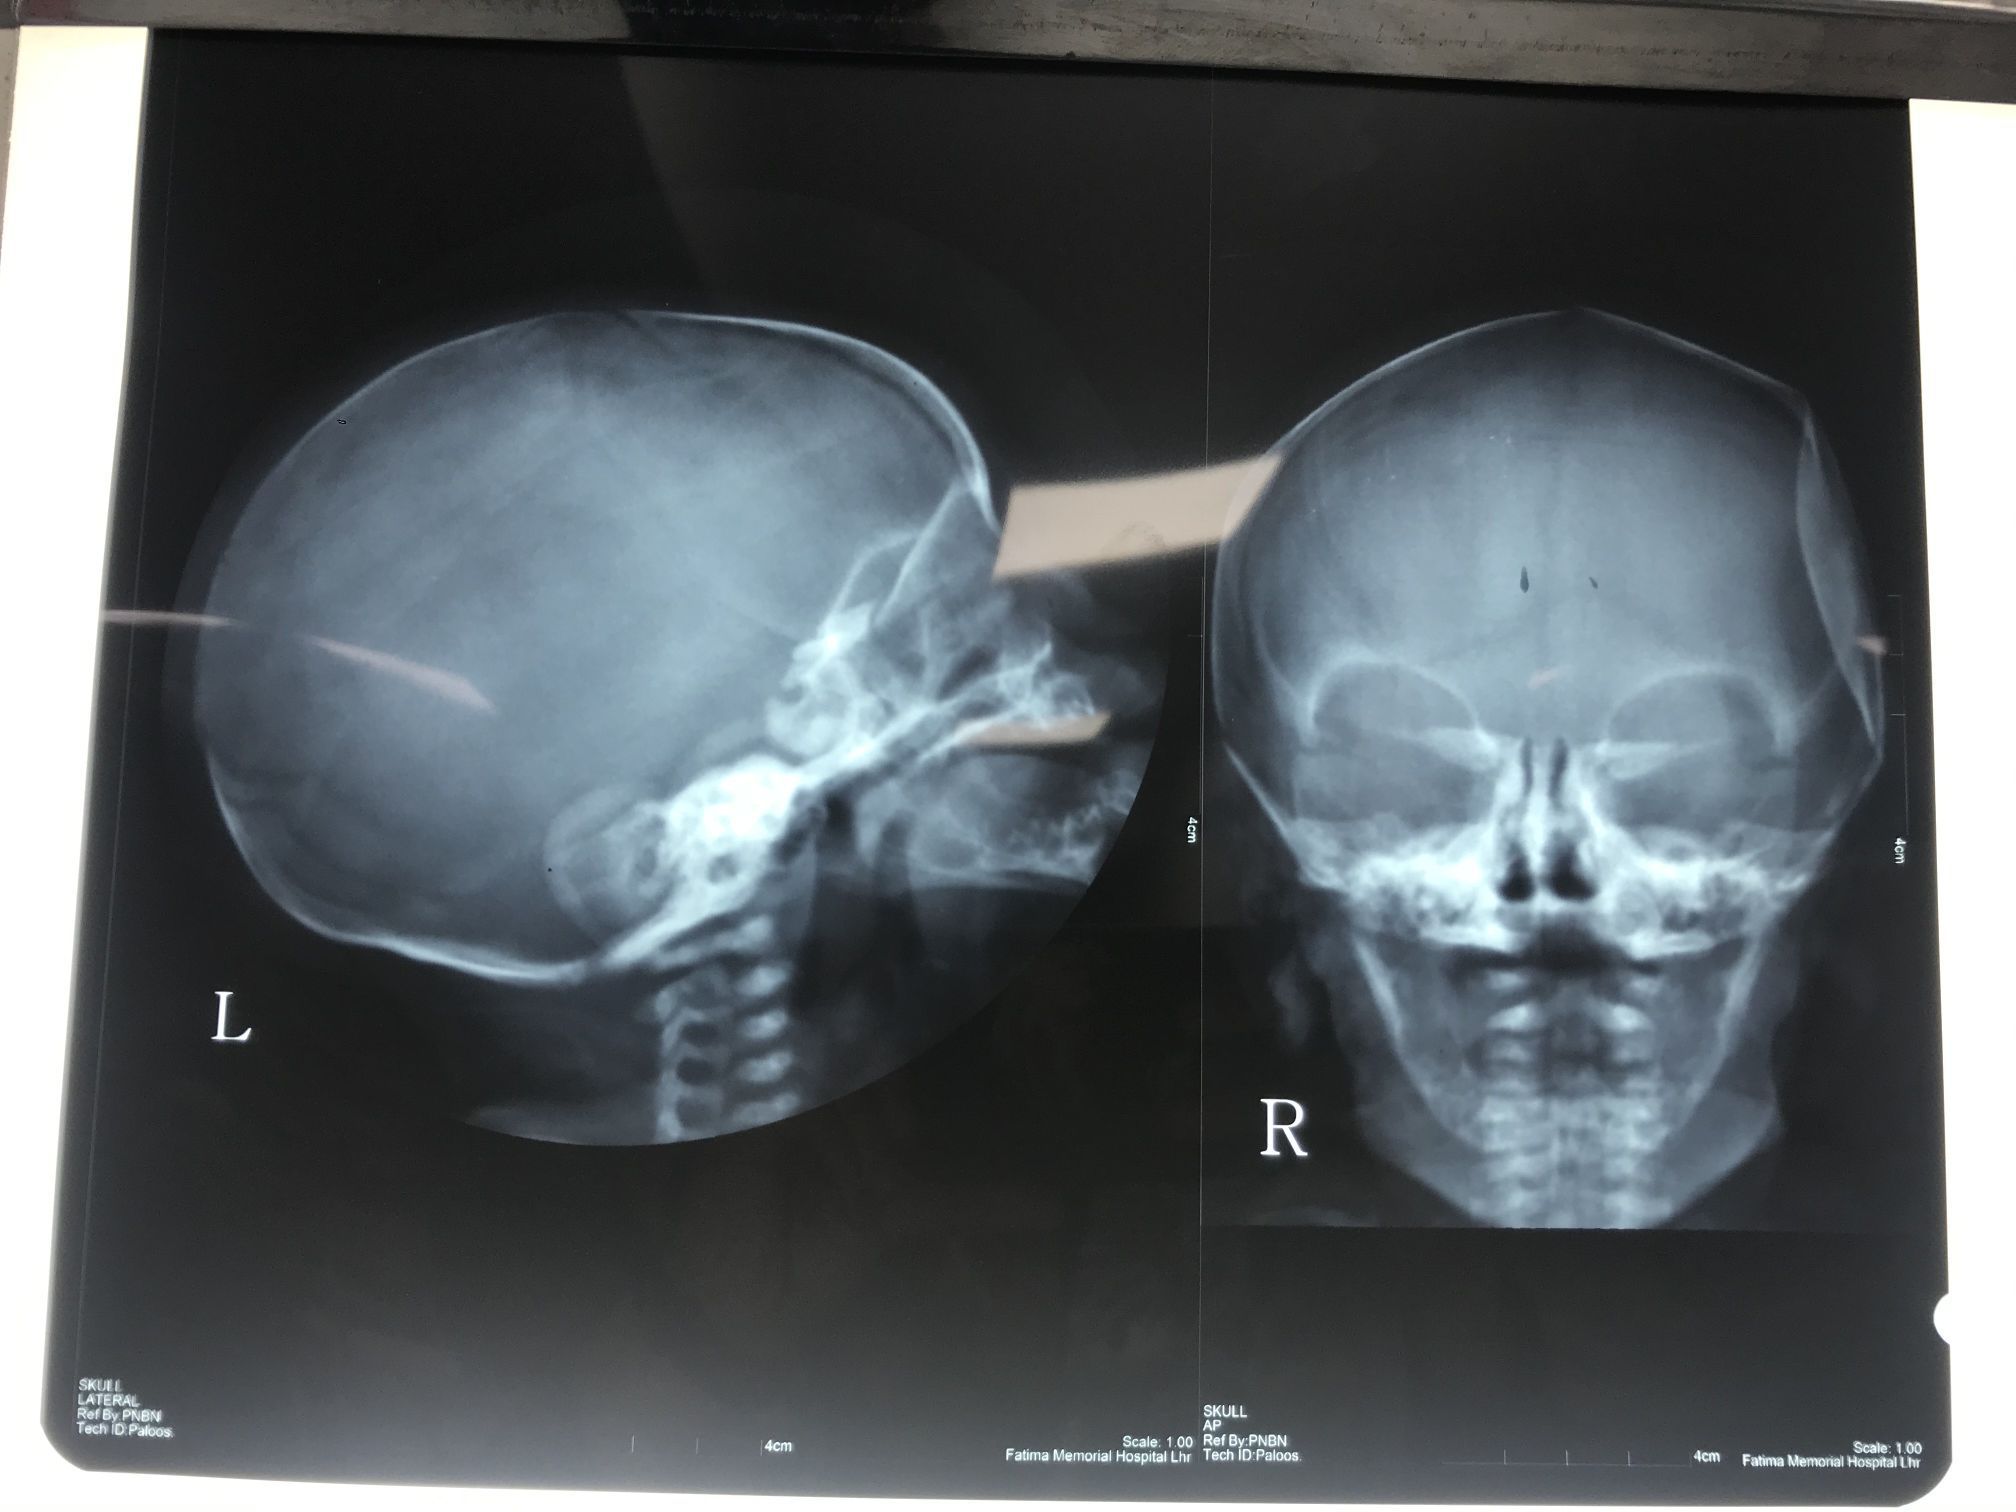

Depressed Temporal Bone

Skull

Neonate